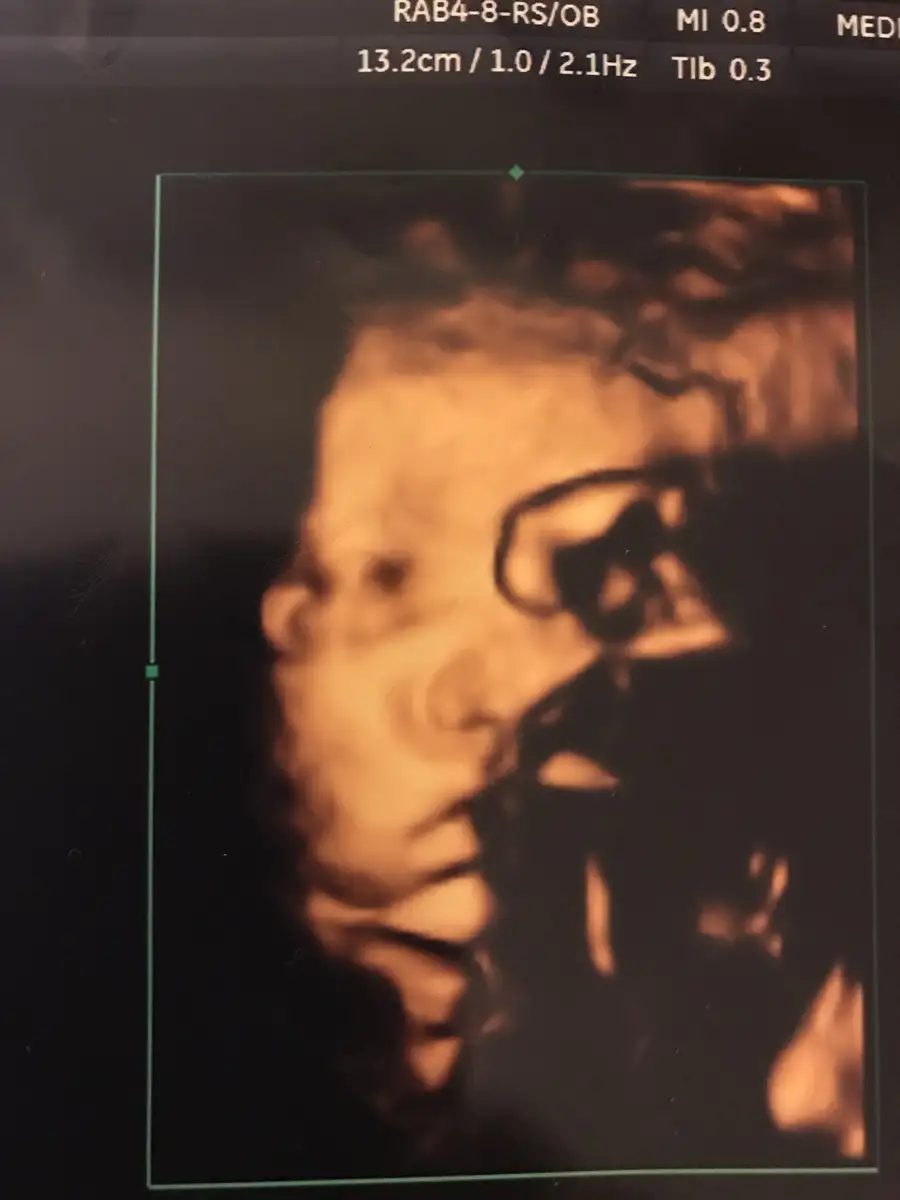

Kizlar bebegimin esi asagida demistim yine baya asagi inmis aksam 5 de lavaboya hittim acayip kanamam oldu acil hastaneye kostuk nst fln yatisim yapildi 34+1 deyim bebegim 2325 kilosu ciger gelistirici igne vurdular sabahada 2. Doz yapilcak riskli dendi yatiyorum eger kanama dsvam ederse doguma alincam dua edin kizlar siniri gectik ama olursada solunum sikintimiz olur heralde

Arkadaşlar size bir sorum olacaktı 34 haftalığım. bebeklerimden biri 1800 diğeri 2000 gr çok mu gerideler bu haftalarda hepinizin bebekleri iki kilo üstü mü yoksa benim gibi olan var mı bir de ultrason ölçüsünden daha küçük olma ihtimali de var korkutuyor beni ikiz olduğu için erken Doğum da olabilir diye solunum sıkıntısı yaşamasalar bile kiloları düşük diye küvöze alırlar mı ki